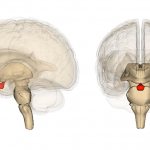

Несмотря на то, что полное восстановление нарушенных нервных клеток в головном мозге невозможно, все же детский орган в какой-то степени способен самовосстанавливаться. Регенерация поврежденной ткани не происходит, но образуются новые связи с осуществлением новых функций старыми нейронами.

Подобные связи образуются лишь в той структуре головного мозга, которая отвечает за память. Остальные функции, возложенные на мозг, необходимо стимулировать, что можно осуществить именно с помощью лечебного массажа и физкультуры.

Работа нервной системы происходит по 2 направлениям: от рецептора к структуре мозга и обратно. С помощью точечного массажа можно вызвать возбуждение определенных структур органа, пробудить их, заставив нормально функционировать.

За счет повышения активности мозговых аналитических центров головного мозга происходит образование новых связей, что влечет за собой восстановление двигательных функций.